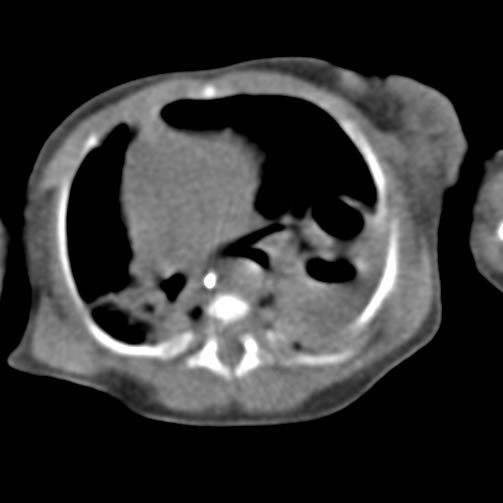

What is image indicative of?

Air fluid level (abcess)